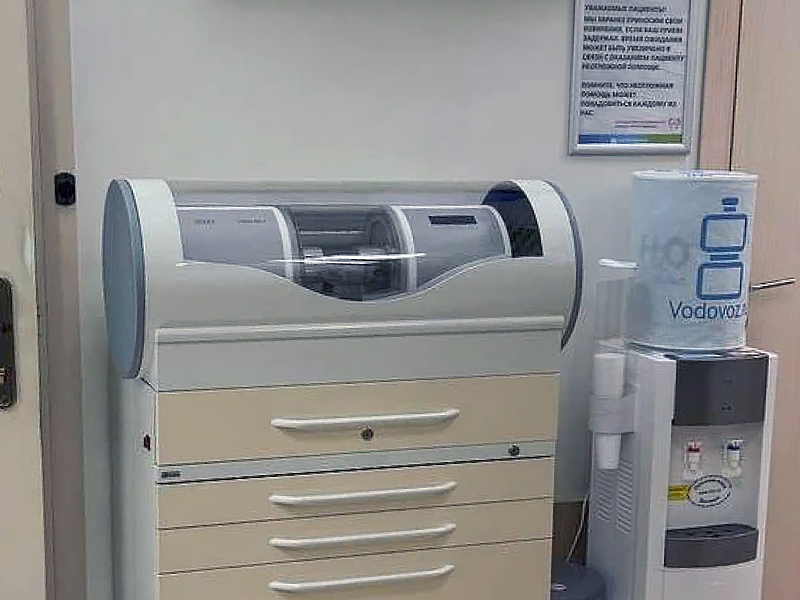

- Анна Альбертовна проводит стоматологическое лечение с использованием микроскопа для максимальной точности и эффективности;